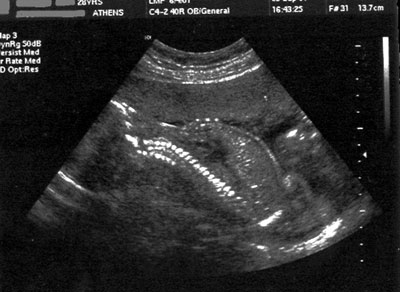

Αξίζει να σημειωθεί ότι από τα 22 περιστατικά της ίδιας μελέτης15 σε 2 διαγνώστηκε μόνο ο εξόμφαλος, σε ένα γαστρόσχιση και σε 3 δεν αναγνωρίστηκε το σύνδρομο, ενώ σε μεταχρονολογημένη επανεξέταση των δεδομένων τους αποδείχθηκε ότι είχαν τουλάχιστον τα 3 από τα 4 μείζονα κριτήρια. Στο περιστατικό της μελέτης μας ο προγεννητικός υπερηχογραφικός έλεγχος θεωρήθηκε φυσιολογικός και έτσι δεν κατέστη εφικτός ο προγραμματισμός του τοκετού. Έγινε υπερηχογράφημα αυχενικής διαφάνειας την 12η εβδομάδα κύησης και υπερηχογράφημα δευτέρου επιπέδου την 22η εβδομάδα, και αναγνωρίστηκε μόνο η κενή ουροδόχος κύστη (εικόνα 6).

6.

Εικόνα 6